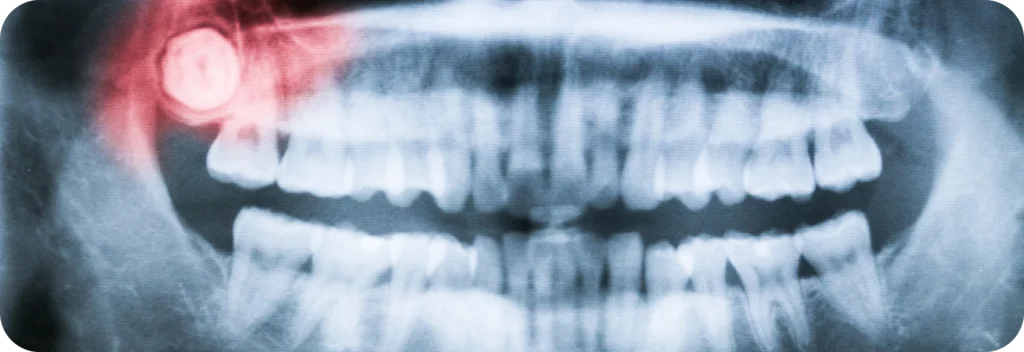

La plupart du temps, les dents de sagesse restent incluses. Toutefois, les canines supérieures présentent également ce problème. D’autres dents peuvent aussi être concernées, bien que cela soit plus rare. L’examen clinique, associé à une radiographie ou un scanner, permet d’établir un diagnostic précis.

Le dégagement chirurgical consiste à libérer une dent bloquée pour permettre son redressement. L’intervention se réalise sous anesthésie locale ou générale, selon les cas. Elle se pratique au cabinet dentaire, dans un environnement adapté.

D’abord, le praticien incise la gencive pour accéder à la dent incluse. Ensuite, il peut retirer une fine couche d’os si la dent est entièrement enfouie. Puis, il pose parfois un dispositif de traction pour guider la dent vers sa place. Enfin, il referme la gencive par des sutures adaptées.